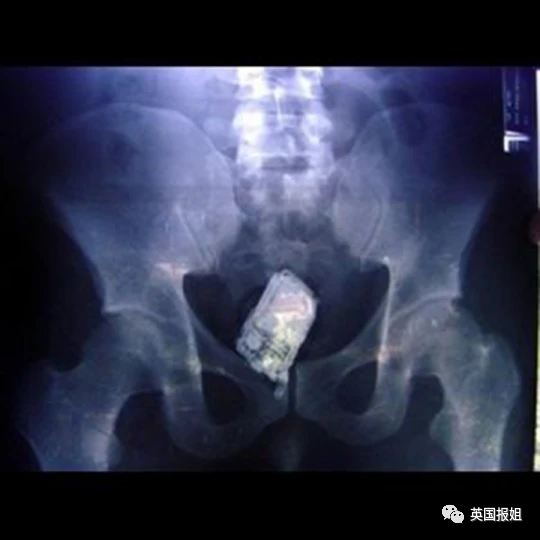

比如手机:新闻报道称这名佐治亚州的忙碌男子,在把手机塞进身体后,仍不断接到电话,导致取出工作一度陷入僵局。